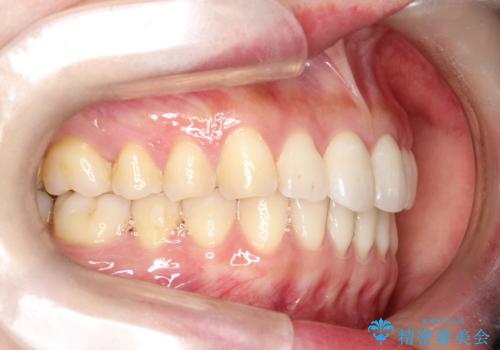

- 前歯の見た目の改善を希望され来院された患者様です。

初診時の歯並びの状態としては、上下にガタガタがある状態であり、特に上の前歯(左上1番)の捻じれを最も気にしていらっしゃいました。

口元の位置も悪くなくスペース必要量も軽度であったため、非抜歯/マウスピース矯正にて治療を行いました。

前歯の捻じれを改善するためにスペースを作る必要があり、前歯の歯の間を削って簡単に直す方法もありますが、奥歯のズレが認められたため、大臼歯後方のスペースを利用し、根本的な原因からしっかりと治療を行いました。

見た目、嚙み合わせ及び、治療期間や施術内容に大変ご満足いただきました。